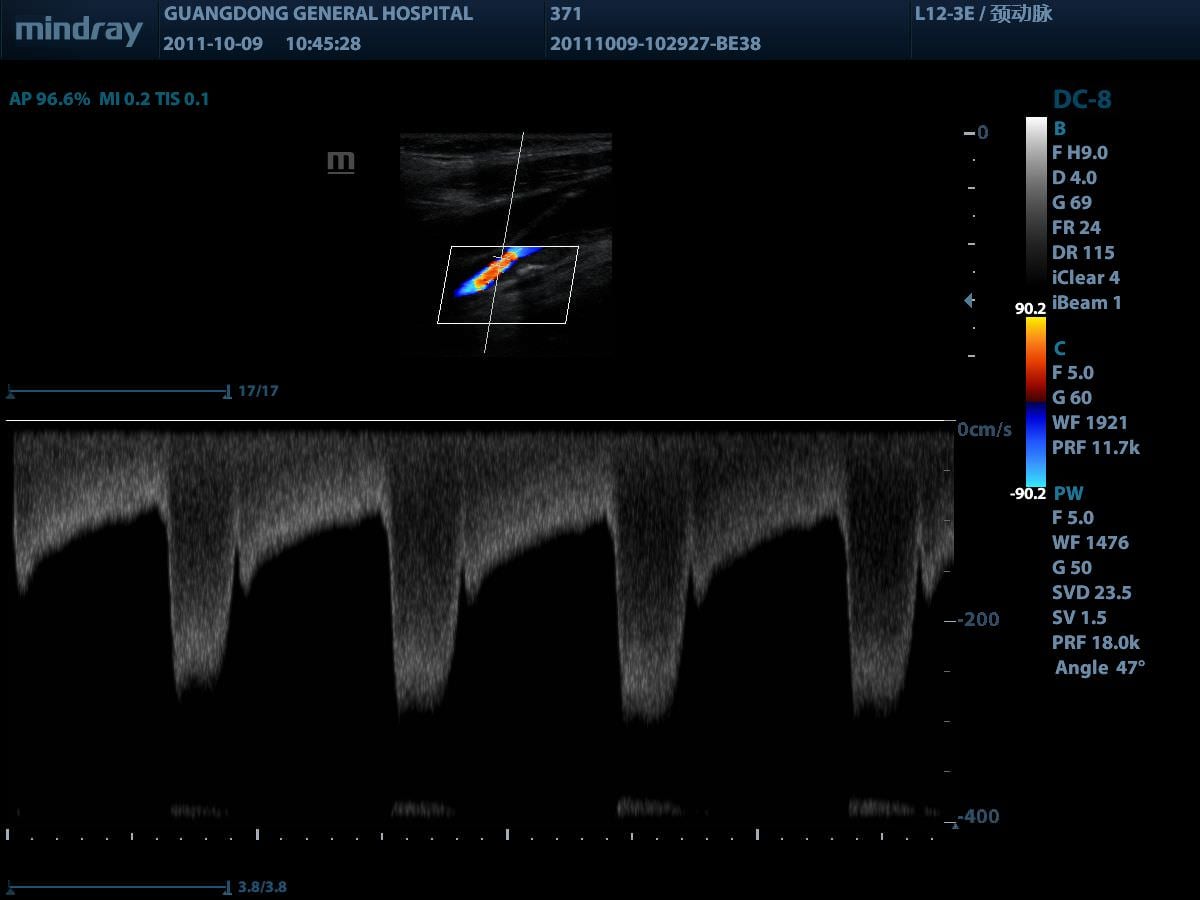

Auto IMT (автоматическое определение толщины комплекса интима-медиа)

Автоматическое измерение толщины передней и задней стенки, предоставляющее точную информацию о состоянии сонной артерии.